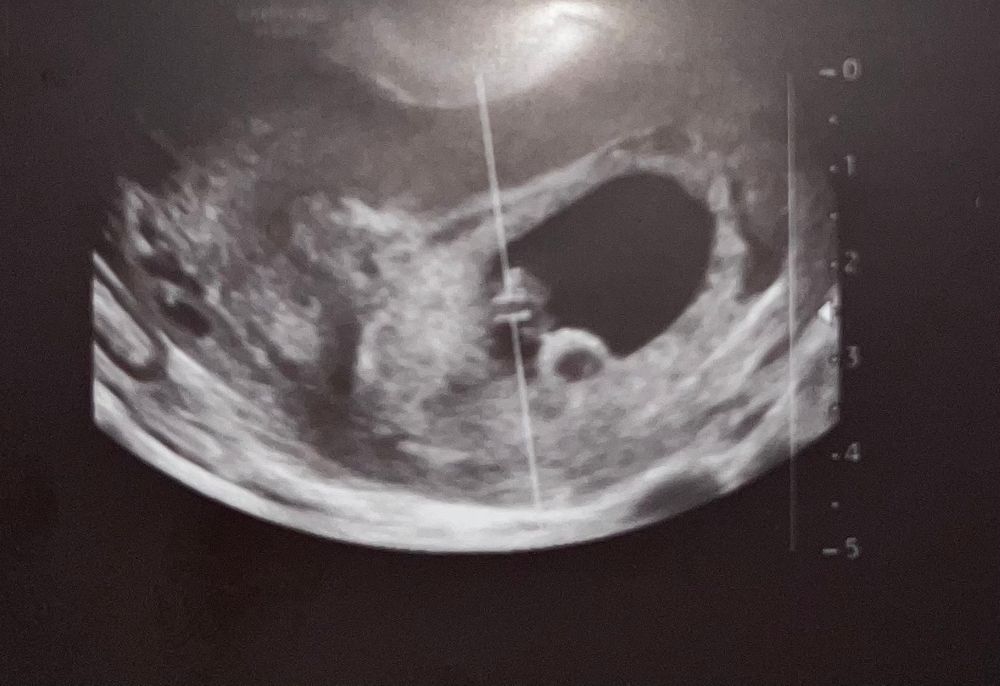

Что это может быть?

Полина Викторовна , сказала, что в динамике посмотрим. Видела такое, но рассасывалось. в прошлый раз мы это тоже видели: думали многоплодная. Сейчас штука подросла 🤷🏻‍♀️

Полина Викторовна , недалеко от эмбриона. В ножках почти.

Дашута, в общем вычислила) это хорионический бугорок)